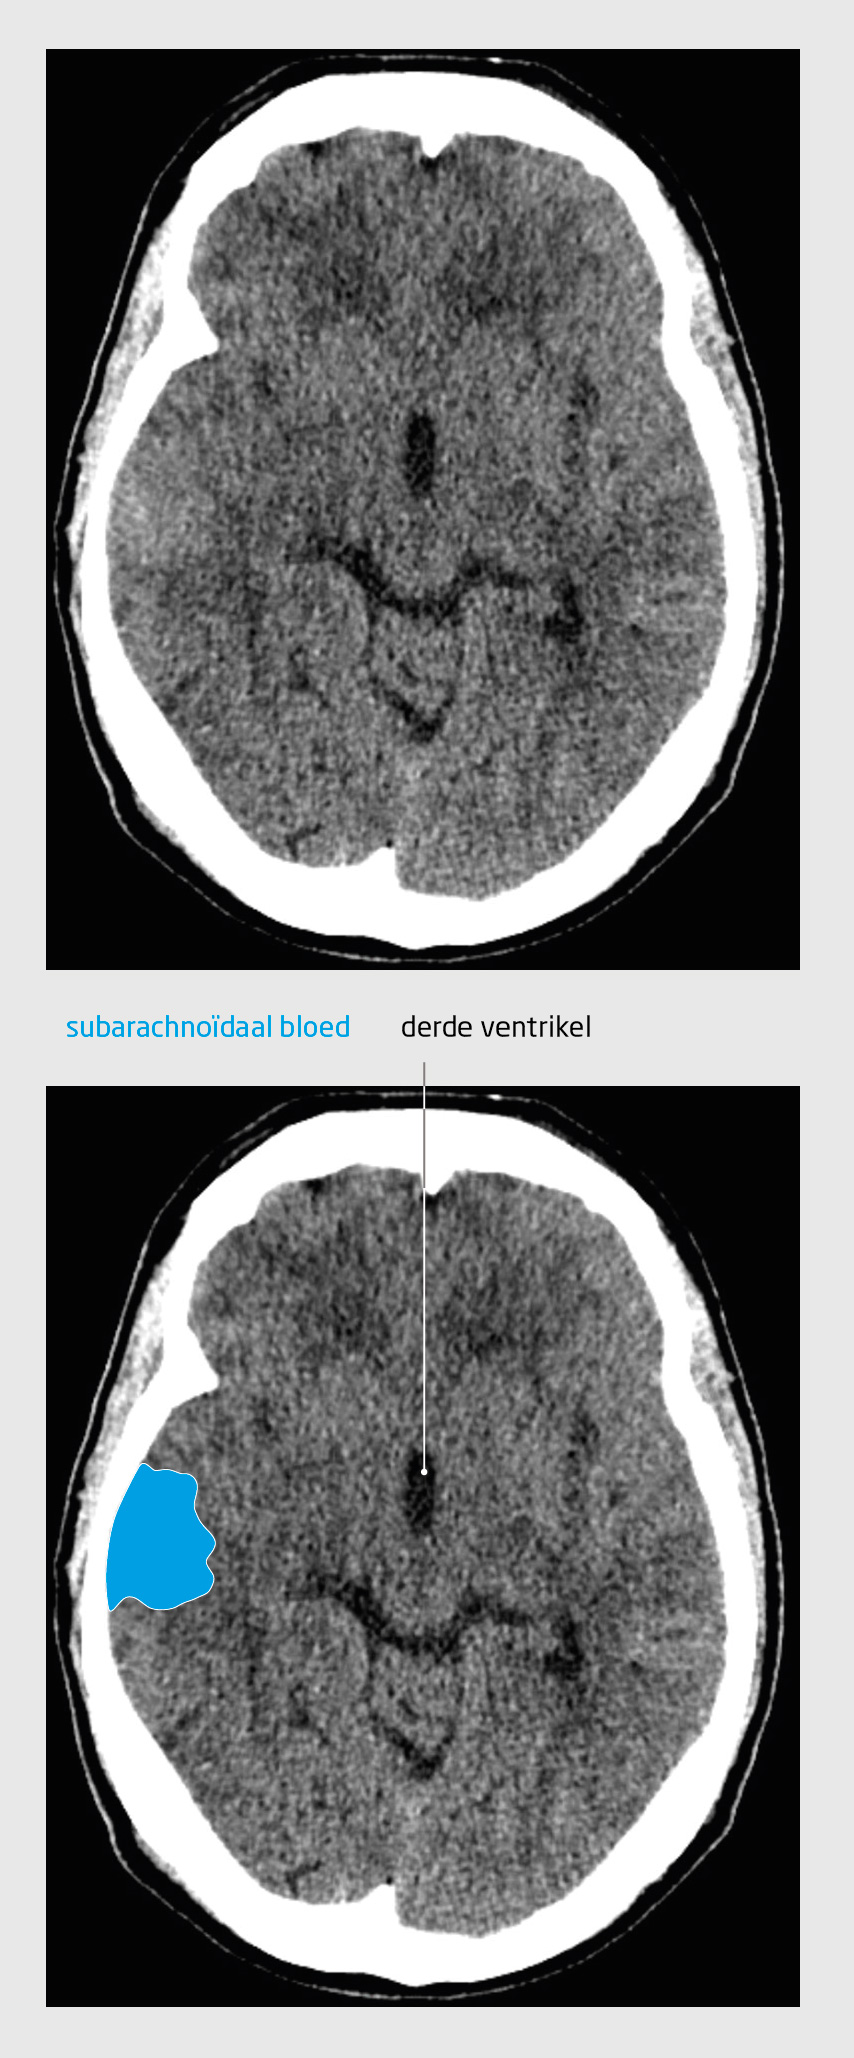

Figuur 2

Subarachnoïdale bloeding

CT-scan van de hersenen van patiënt B

Figuur 2 | Subarachnoïdale bloeding | CT-scan van de hersenen van patiënt B

De CT-hersenen van patiënt B toont subarachnoïdaal bloed rechts temporaal. De verstreken tijd sinds het begin van de hoofdpijn heeft er waarschijnlijk voor gezorgd dat een deel van het bloed – met name in de basale cisternen – al is geresorbeerd.

Bij lichamelijk onderzoek zagen wij een apathische man met een apraxie. De rug was aan de onderzijde paravertebraal drukpijnlijk, rechts meer dan links, zonder aanwijzingen voor radiculaire prikkeling. Patiënt had een breedbasisch en instabiel gangpatroon en bij het lopen neigde hij achterover te vallen. Wij verrichtten een CT-scan van de hersenen, die hyperdense afwijkingen rechts temporaal liet ziet, passend bij een doorgemaakte subarachnoïdale bloeding (figuur 2). Wij verwezen patiënt met spoed naar een interventiecentrum. Aldaar werd bij CT-angiografie een aneurysma van de A. communicans posterior gezien, dat succesvol endovasculair behandeld werd. Bij controle 2 maanden na het bezoek aan onze polikliniek was patiënt volledig klachtenvrij.